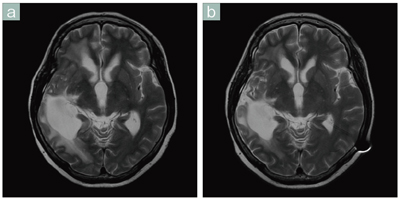

■症例3 Ready BrainによるT2強調画像(水頭症)

同一患者のT2強調画像。

a:水頭症の治療前,b:治療2か月後。わずかな断面のズレはあるが良好な再現性が得られている。Ready Brainを用いることで継時的な変化を客観的に観察することができ,患者さんにも病状をわかりやすく説明できる。